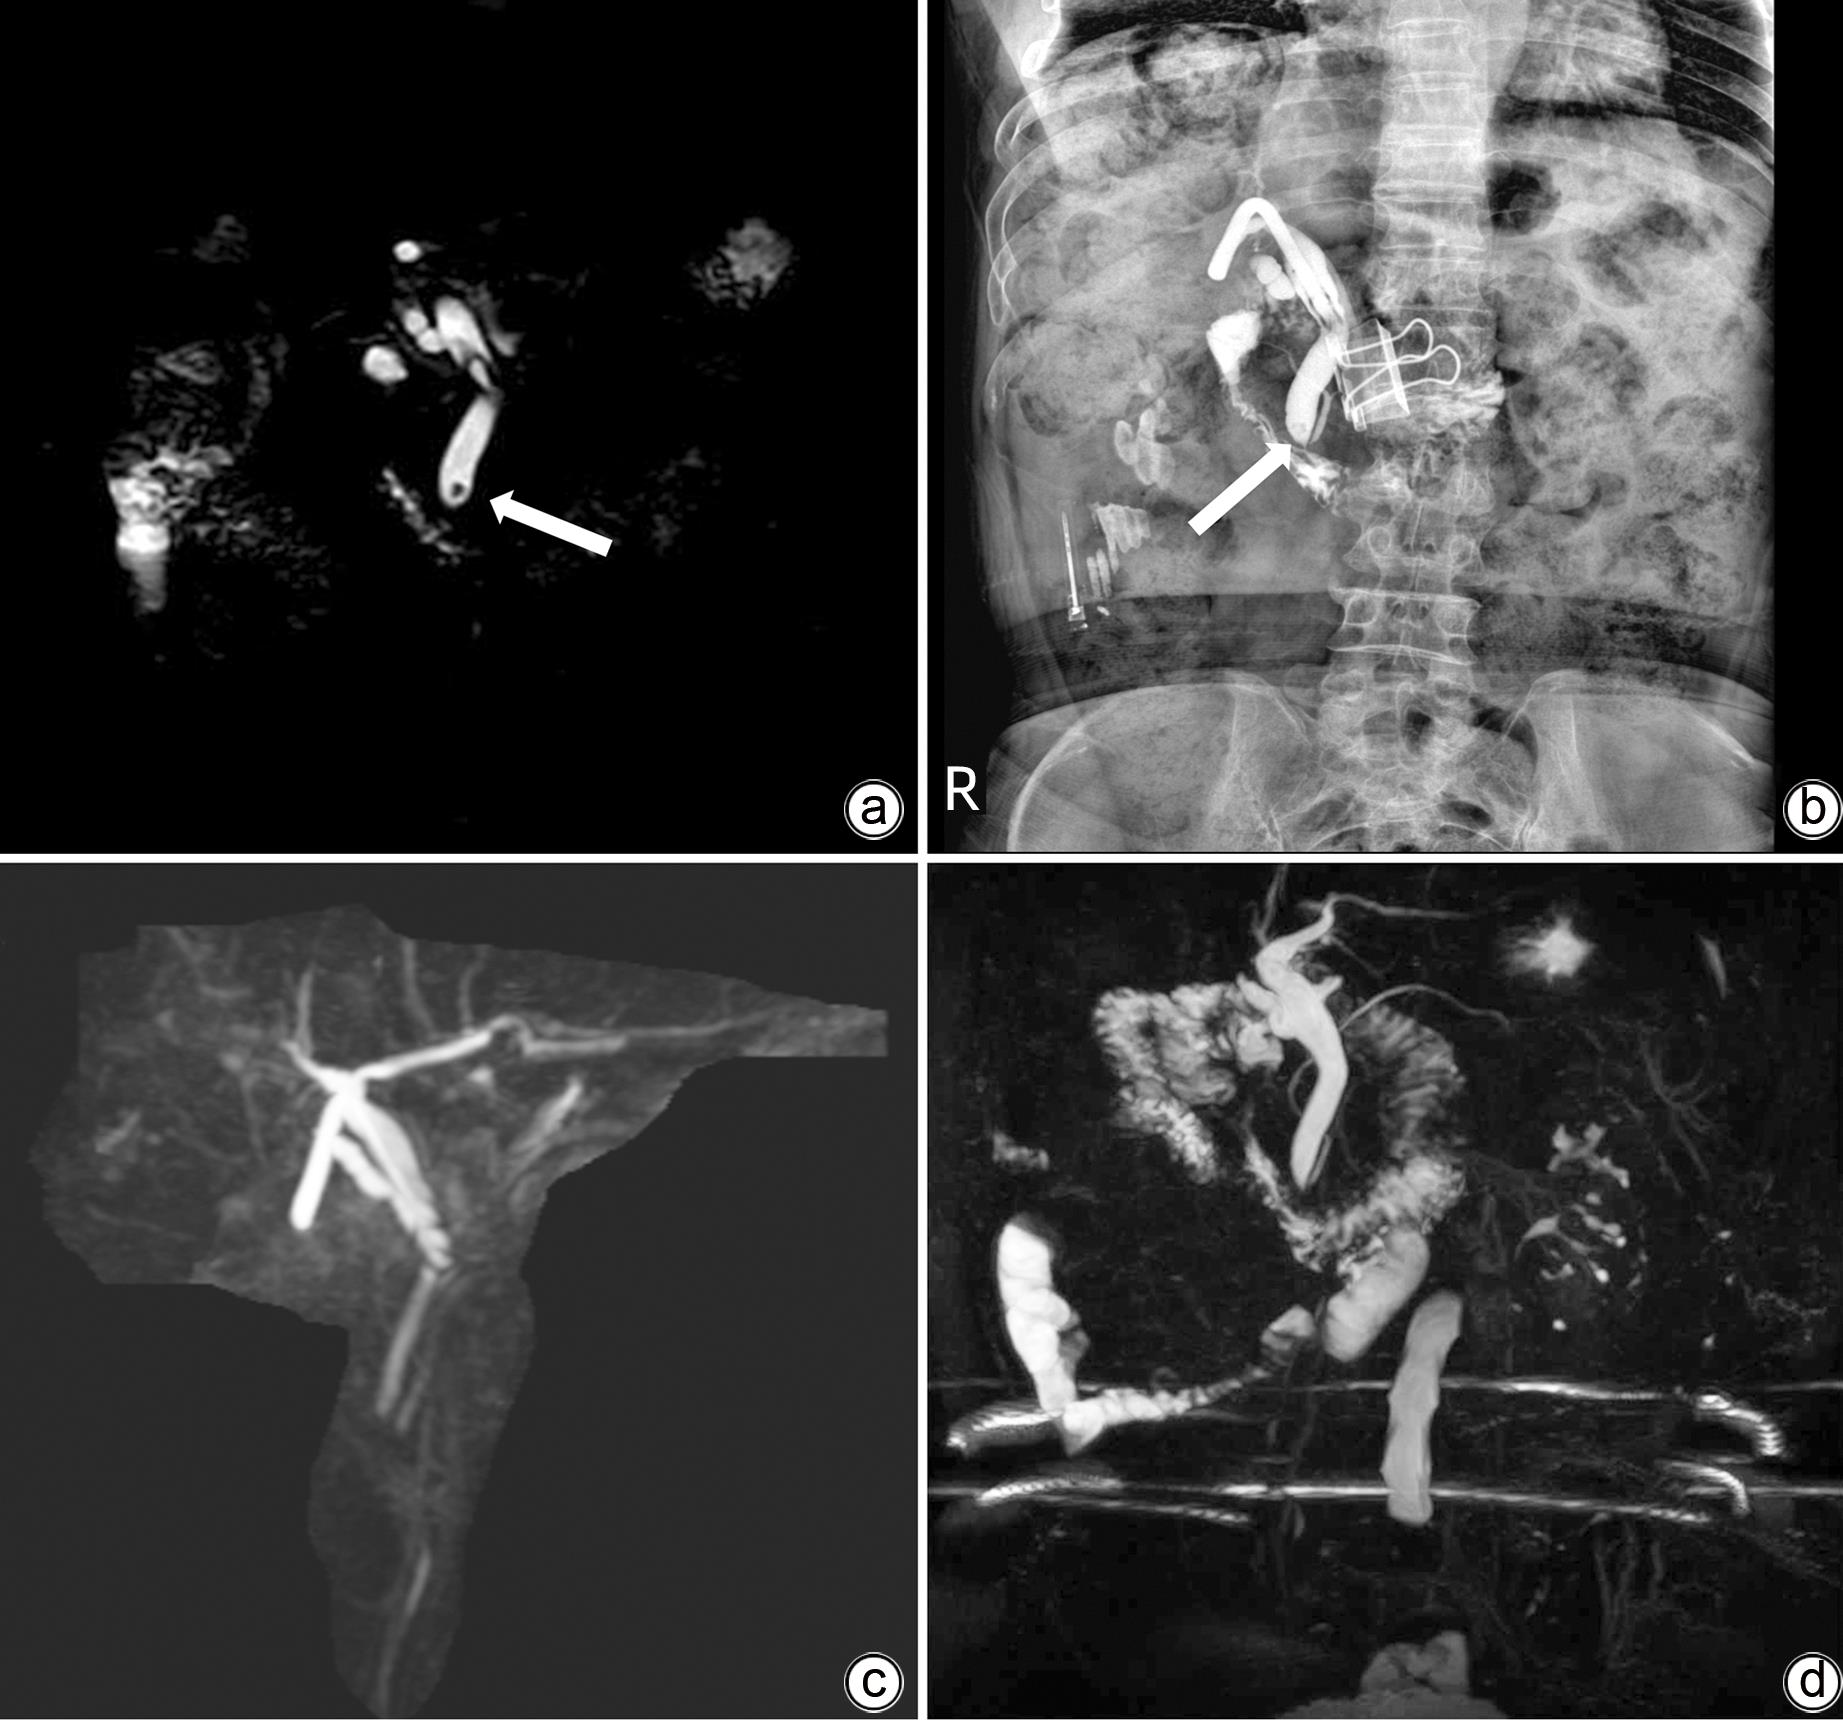

T-tube flexible ureteroscopy in treatment of residual choledocholithiasis A case report

Shihong CHEN, Dong WU, Hong WEN, Yuanjun CHEN, Gang CAO

2023, 39(9): 2179-2184. DOI: 10.3969/j.issn.1001-5256.2023.09.022

Abstract(891) HTML (254) PDF (989KB)(64)

Abstract:

At present, endoscopic retrograde cholangiopancreatography (ERCP) and T-tube sinus tract lithotomy are the main treatment methods for residual choledocholithiasis after surgery. However, these treatment methods have certain drawbacks; for example, ERCP may cause complications such as postoperative pancreatitis, bleeding, and perforation, and T-tube sinus tract lithotomy may cause sinus tract injury and bleeding. As a commonly used instrument in urology, flexible ureteroscope has the characteristics of small diameter and flexible angle and thus has a good prospect in the treatment of common bile duct stones. A patient with common bile duct stones was successfully treated by flexible ureteroscopy combined with a stone basket in Department of General Surgery, The Second People’s Hospital of Guizhou Province. Up to now, the patient has been followed up for seven months with no special discomfort, and magnetic resonance cholangiopancreatography showed no common bile duct stones.